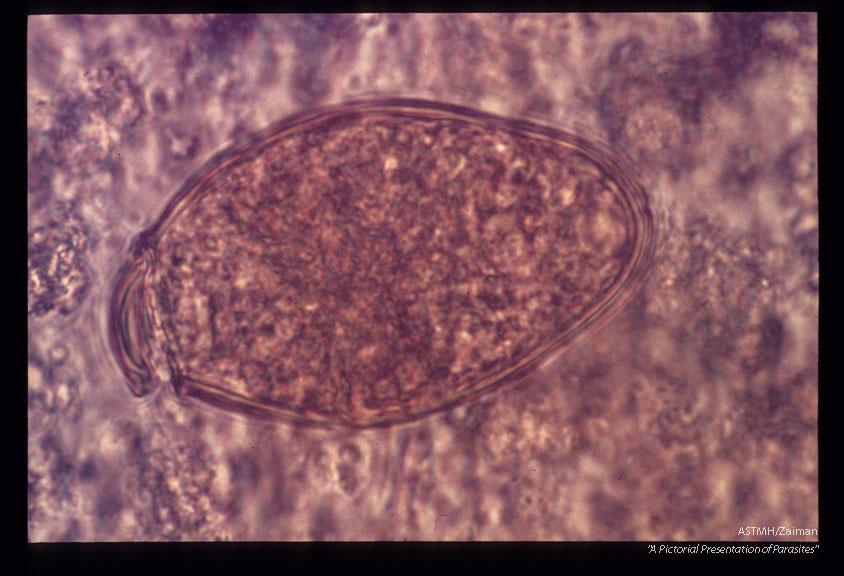

Eggs in stool.

Paragonimus

Description: Eggs in stool.